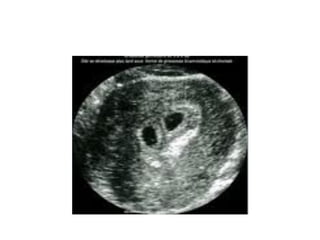

• Échographie +++

• Premier trimestre :

– Garant d’un diagnostic précoce

– Permet un diagnostic facile (2 embryons)

– Décrit le type anatomique (BA, MA…)

• Deuxième trimestre :

– Permet de poser le diagnostic

– Étude morphologique des fœtus (malformations)

– Biométrie des deux fœtus (croissance des fœtus)